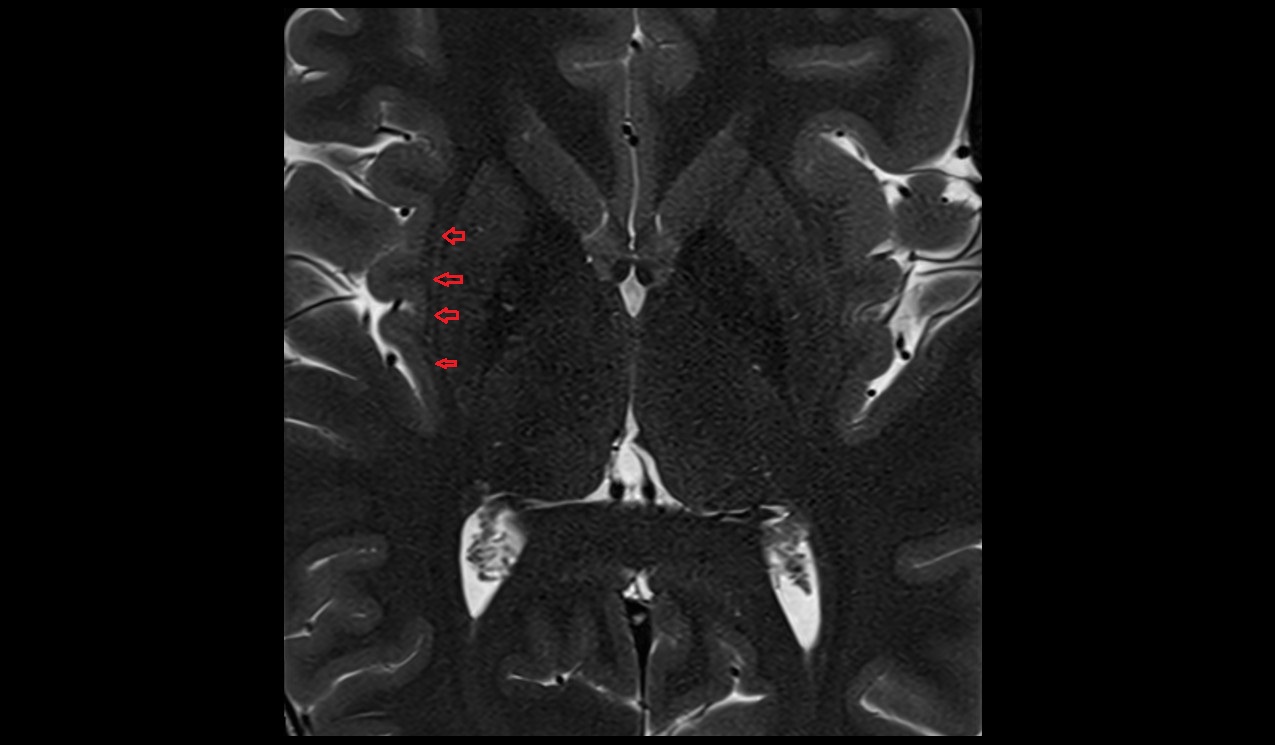

- Body of hippocampus

- Head of hippocampus

- Tail of hippocampus

- Hippocampus